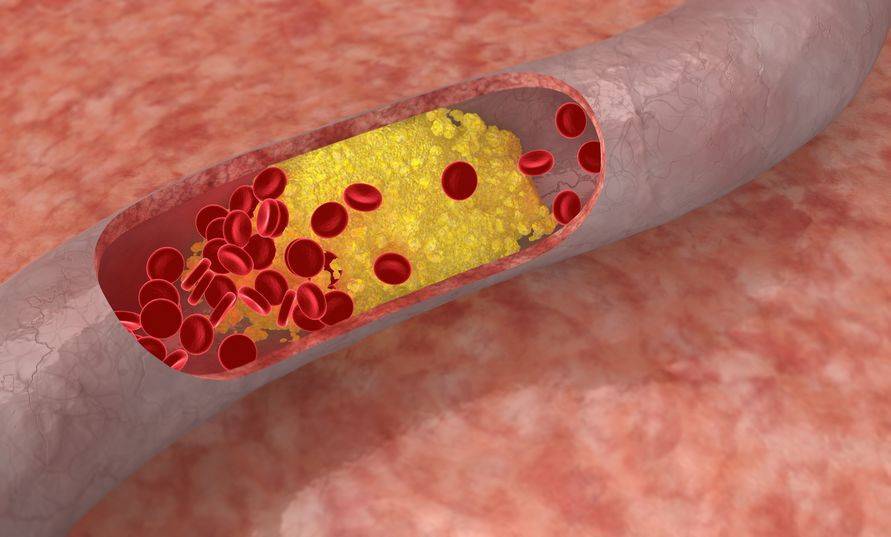

眾所周知,血管是運輸血液和營養物質的通道,只有血管通暢時才能夠保證血液的正常流動。

可如果平時存在抽菸的習慣,則會損傷血管內壁,而且香菸中還含有較多的一氧化碳和尼古丁,容易降低血液吸收氧氣的能力以及促使血壓升高,心跳加快;

在多重因素的影響之下,血液循環便會受阻,長此以往心髒的負擔越來越重,最後則會出現心肌缺血所引起的冠狀動脈阻塞問題。